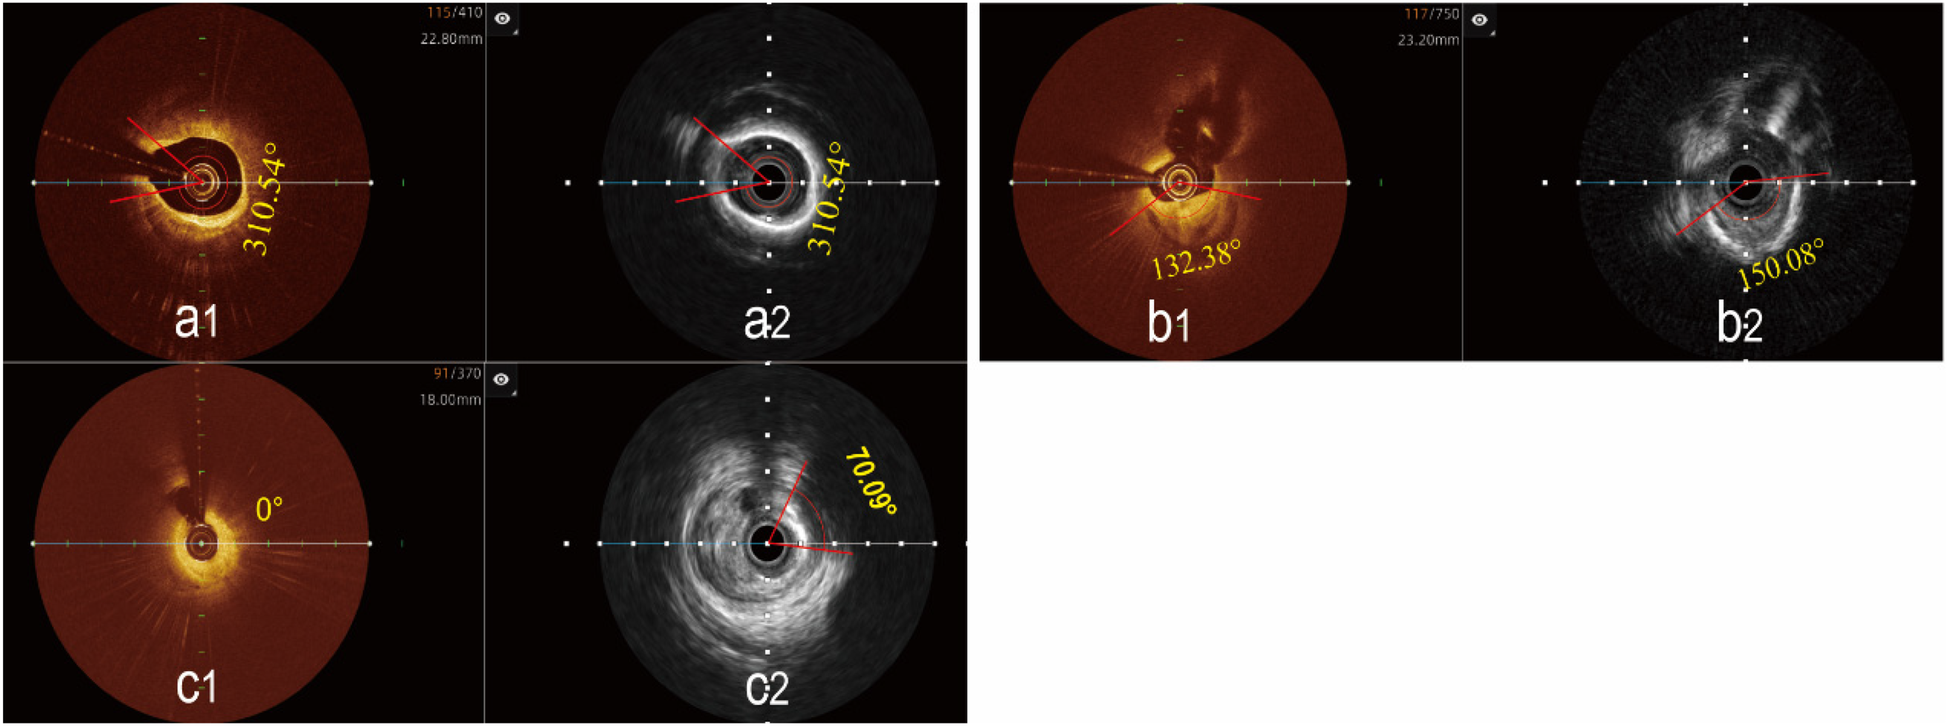

Figure 5

Determination of the maximal calcified plaques arc using the hybrid IVUS-OCT imaging system. (a1,a2) The maximal arc of calcification is the same in both images; (b1) OCT shows a smaller maximal arc of calcification than IVUS b2; (c1) OCT cannot display calcified plaque, (c2) IVUS shows the maximal arc of calcification.